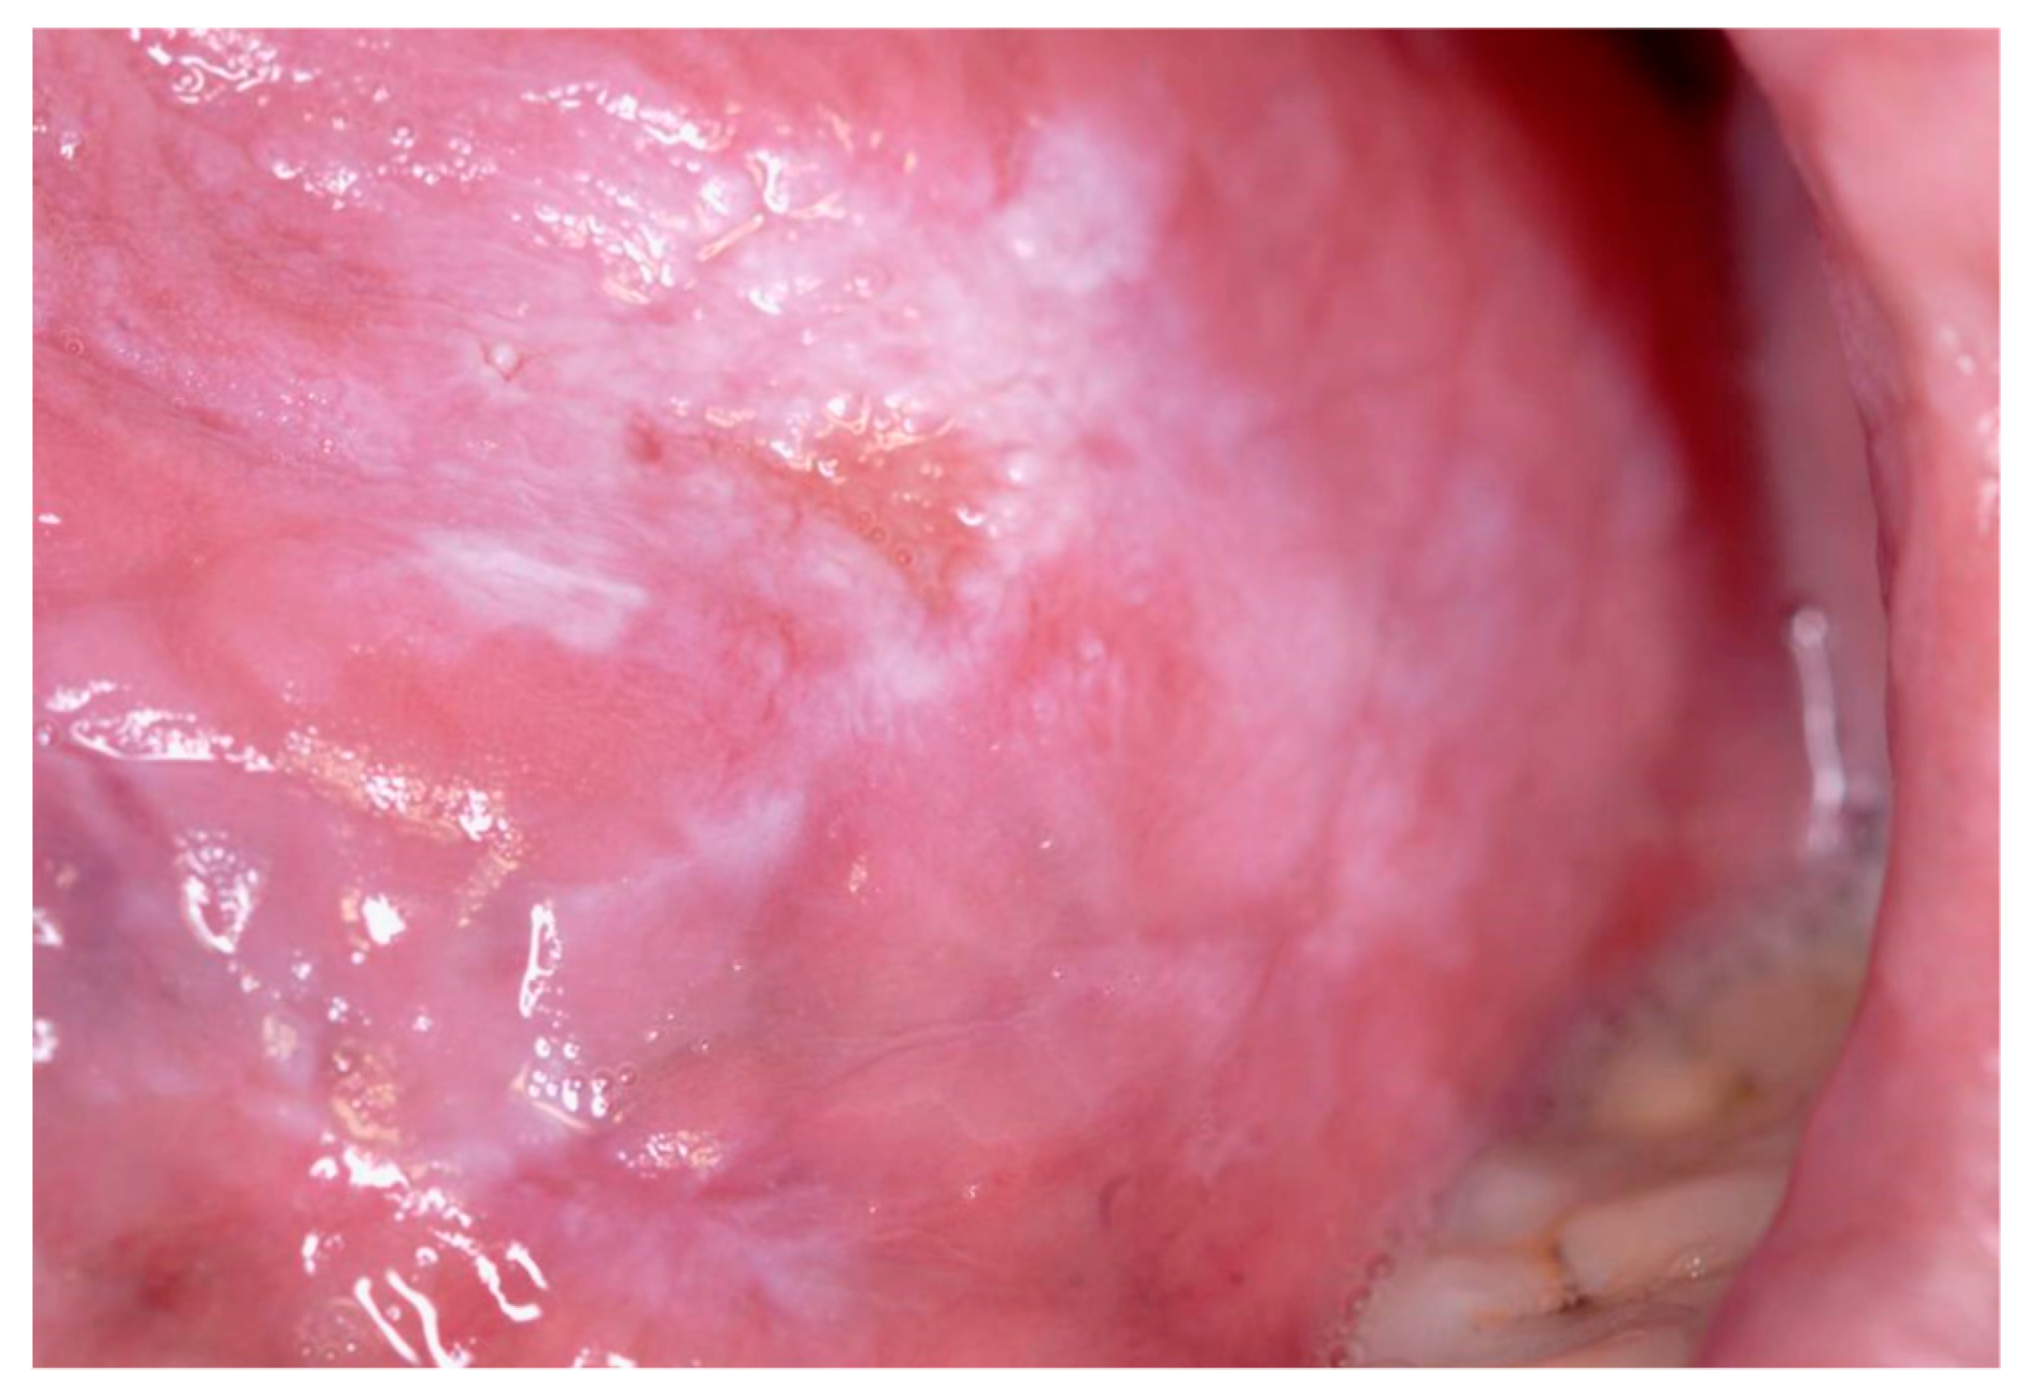

Oral leukoplakia. A More Challenging Disorder than It Seems †